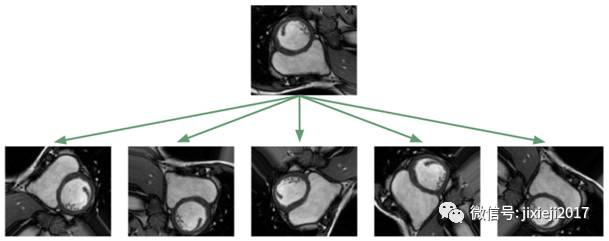

分割这些MRI对于未经专门训练的人来说是非常困难的:

利用深度学习方法解决这个问题,面临的最大挑战是数据集太小。数据集仅包含如上图所示的243张医师已分割的、来自有16例患者的MRI图像。另外还有3697个未标记图像,它们对于无监督或半监督学习可能有用的,但这个项目是一个监督学习的问题,我不考虑使用这些图像。图像大小为216×256像素。

对于较小的数据集,人们对于模型泛华到没见过的图像的效果是不抱希望的! 不幸的是,医疗环境中的典型情况就是如此,昂贵的标记数据和的难以获取的数据。通用的流程是应用仿射变换增强数据:随机旋转,平移,缩放和剪切。此外,我还应用了弹性形变,局部拉伸和压缩了图像[2]。

应用这种图像增强算法的目的是为了防止神经网络只记住训练的样例,并强迫其学习RV是一个实心的、月牙形的、方向任意的物体。在我实现的训练框架中,我会随时对数据集应用图像变换算法,这样,神经网络就会在每次训练时看到新的随机变换。